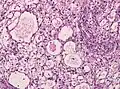

Микрокистозная менингиома содержит большое количество микрокист, окружённых опухолевыми клетками звёздчатой формы[8].

Хордоидная менингиома Микрокистозная менингиома

Микрокистозная менингиома